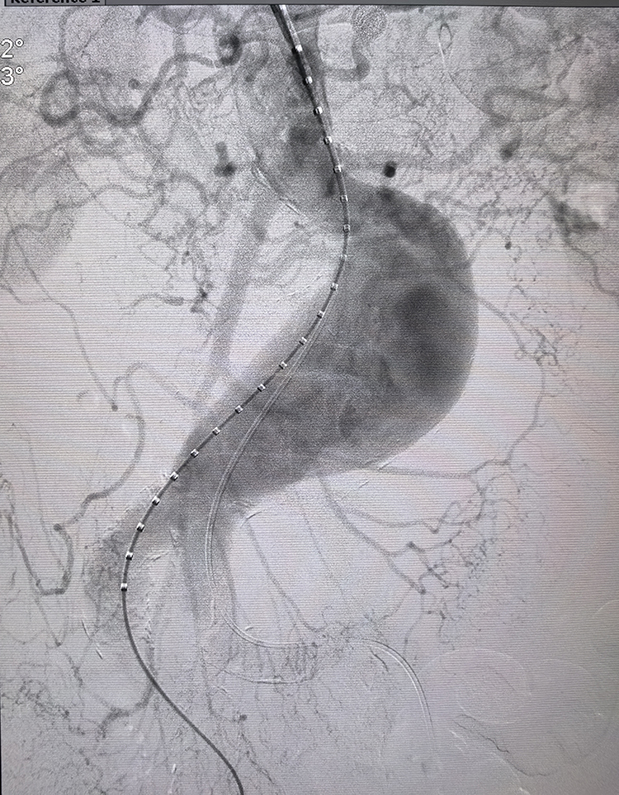

普外科五病区副主任医师雷俊接到会诊通知后立即赶到急诊科,在查看患者抢救情况与初步体征后,与急诊科医护人员一同全程护送程先生前往影像科完成CTA检查。检查结果清晰显示:程先生确诊为腹主动脉瘤破裂伴出血、腹膜后血肿、右侧髂内动脉假性动脉瘤;进一步测量发现,瘤体长约10cm、直径达6cm,且瘤体紧邻肾动脉开口,存在锚定区短、梯形短瘤颈、髂动脉极度扭曲等复杂解剖结构,这意味着手术不仅要精准隔绝瘤腔止血,还要严格避开肾动脉以防肾功能损伤,手术风险与操作难度极大。

针对程先生的危急病情,普外科五病区曹志国主任组织多学科团队快速研判,确定“腹主动脉覆膜支架植入术 + 髂内假性动脉瘤栓塞术”方案并明确分工。手术过程中,多学科团队紧密配合,在影像设备引导下精准完成核心操作,成功为患者植入腹主动脉覆膜支架并栓塞髂内假性动脉瘤,精准隔绝瘤腔、控制出血,患者术中生命体征始终平稳,手术顺利完成。